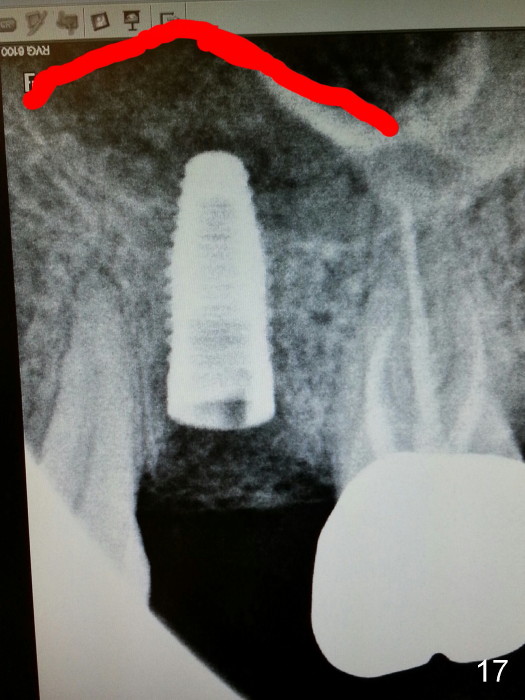

Grafting Following Immediate Implant (Photos Provided by Xue Steven, DDS)

The tooth #13 appears to be affected by periodontits and occlusal trauma (Fig.1*). After using a periotome (Fig.2), the tooth is extracted (Fig.3). The buccal flap is raised (Fig.4). Gingival graft is to be harvested from the site of #15 (Fig.5). The tissue is elevated buccally (Fig.6) and separated (Fig.7). The donor site is covered by a collagen membrane (Fig.8*). A diamond bur is used to induce bleeding from the socket (Fig.9*). Osteotomy is initiated (Fig.10) and enlarged (Fig.11,12). A tapered implant is being placed (Fig.13-15) following internal sinus lift (Fig.16,17). The implant is placed subcrestally, followed by bone graft (Fig.18), soft tissue graft (Fig.19), and suturing (Fig.20 <, Fig.21).